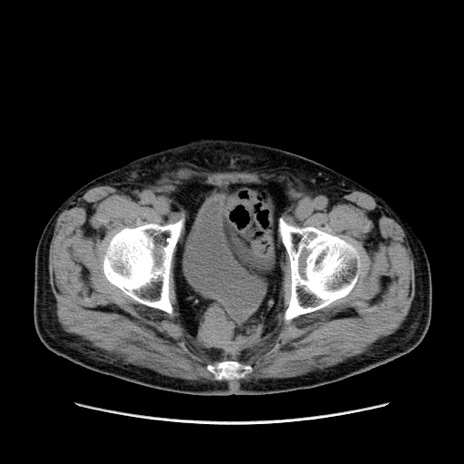

症例24(横断像)

【症例】80歳代男性

【主訴】左側腹部痛、嘔吐

【現病歴】本日早朝より左腹部に痛みあり。昼頃嘔吐認めたため、救急要請。

【既往歴】直腸癌(Mile手術)、胆摘

【身体所見】意識清明、BT 35.9℃、BP 221/93mmHg、SpO2 97%(RA) 、腹部:左ストーマ周囲に限局性の腹部膨隆あり。 膨隆部自発痛・圧痛あり・軟。

【データ】WBC 7700、CRP 0.09